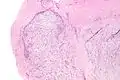

| Micrograph of nodular fasciitis showing the haphazard arrangement of cells (tissue culture-like pattern). H&E stain. | |

The microscopic histopathology of hematoxylin and eosin stained nodular fasciitis tumors (see above and three below figures) consists of spindle-shaped myofibroblastic cells (i.e. cells with features of smooth muscle cells and fibroblasts.).[8] These cells are in a myxoid (i.e. more blue or purple compared to normal connective tissue because of excessive uptake of the hematoxylin stain) or a collagenous (high content of collagen fibers) tissue background. The neoplastic myofibroblasts are arranged in whorls and/or short bundles. These cells may show high rates of replicating as judged by their mitotic index but these mitoses are normal in appearance. The tumor tissues often contain red blood cells, lymphocytes and giant osteoclast-like giant cells and may contain sites of bone-like tissue.[10] NF is sometimes classified into three subtypes based on its predominant histopathological pattern: myxoid or reactive (type I), cellular (type II), and fibrous (type III).[4] These patterns appear related to the duration of the lesion with the myxoid variant tending to have the shortest duration and the cellular and fibrous variants tending to have progressively longer durations.[14]Immunohistochemical analyses indicate that the cells in NF usually express smooth muscle actin, muscle specific actin, and vimentin proteins but generally do not express CD34, S-100 protein, desmin, trypsin, factor VIII, F4/80 (also termed macrophage-specific antigen), or HLA-DR1 proteins.[10] Uncommonly, the cells in NF tumors also express the CD68 (a histiocyte-specific marker) protein.[4]